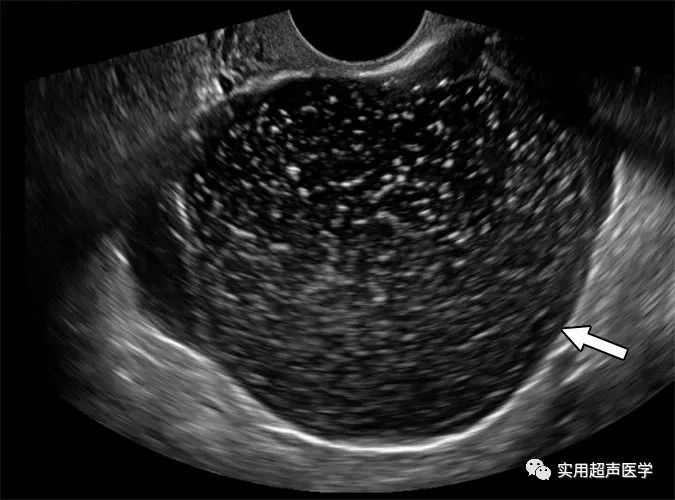

56岁女性,伴有隐性腹痛和边缘浆液性肿瘤。超声图像显示 10.5 cm 右侧卵巢单房囊性病变,伴有与 O-RADS 3 病变一致的散射内部回声(箭头)。